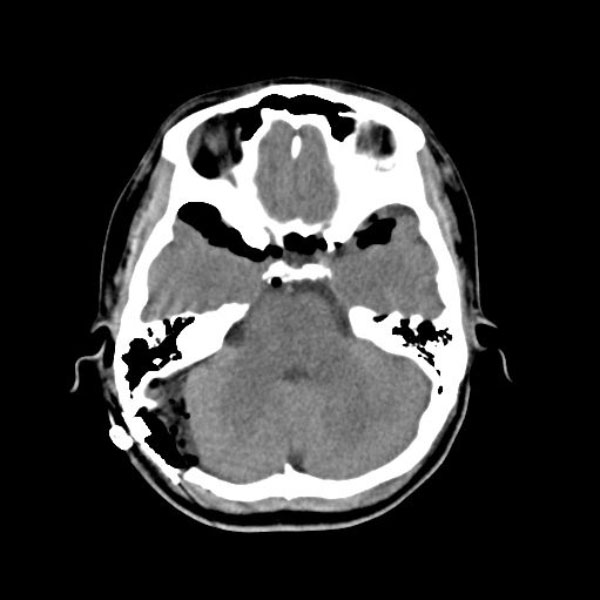

症例 '26年2月

No.

579

大阪府の病院

'26年2月

40代

右三叉神経痛

(顔面の痛みをとること)

手術前

減圧前

減圧後

術後血管撮影